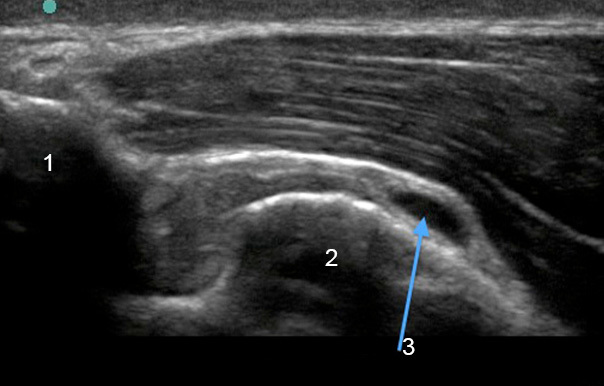

Imagen de bursitis subacromial del hombro

Acromion

Tuberosidad mayor

Bursitis subacromial